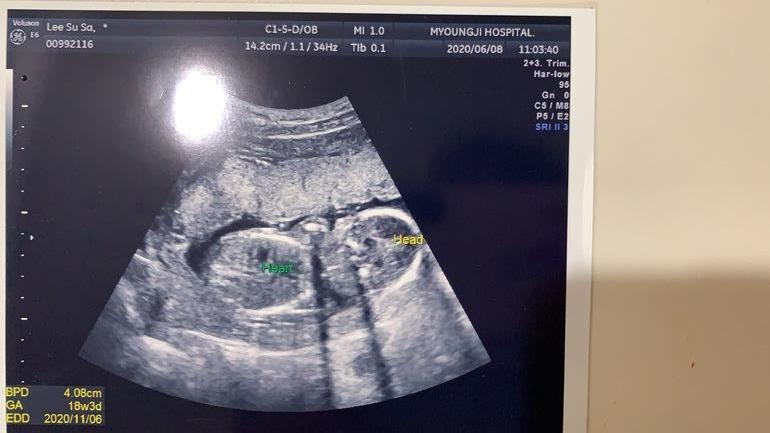

УЗИ, КТГ, доплерВ прошлый раз была у врача ровно в 15 недель. Клинику пока решили не менять, ходим к старому врачу, - он намного опытнее.Тогда всё посмотрели, сказали что норма и отпустили. Наш врач на первом скрининге пол не предполагал, а в 15 недель малыш скрестил ножки, а потом и вовсе отвернулся😌Вчера, поскольку срок 18 и 2 по месячными и 18 и 3 по УЗИ врач сказал сдавать тройной тест. Результаты будут в конце недели, так что остаётся только ждать. По УЗИ всё в норме, но врач говорит, что похоже на девочку. Я даже растерялась как-то, ожидала что подтвердят нам мальчика и начну уже потихоньку что-то выбирать малышу, но наш врач сказал что ничего мальчикового не видит🤷♀️И если раньше мы с мужем больше хотели девочку, то сейчас уже привыкли и полюбили мальчика внутри, над именем думали, а тут...)Придётся ждать ещё 3 недели, видимо. Но это не главное, конечно. Главное, чтобы малыш был здоров🙏Фото УЗИ 15, 18 и 13 недель ( на 13-ой неделе другая клиника)